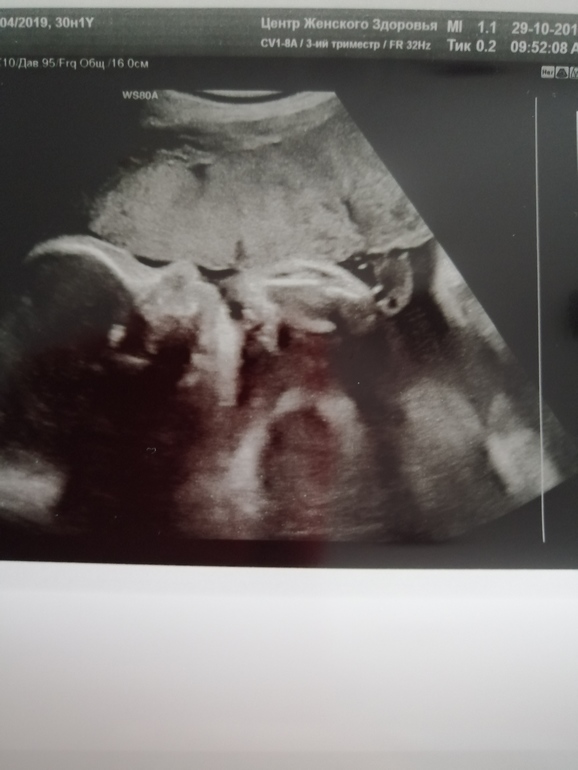

Малышка уже 1400,головкой повернулась, моя сладкая💞

Всё узи лежала отвернута, только узистка проговорила, что никак не получится фотку сделать, как малышка тут же поворачивается🤭 фоткай говорит)))) несколько раз зевнул, высунула язычок, потом засунула ручку в ротик)) такая прелесть все это наблюдать 😍

Вот моя сладенькая носопырочка🥰